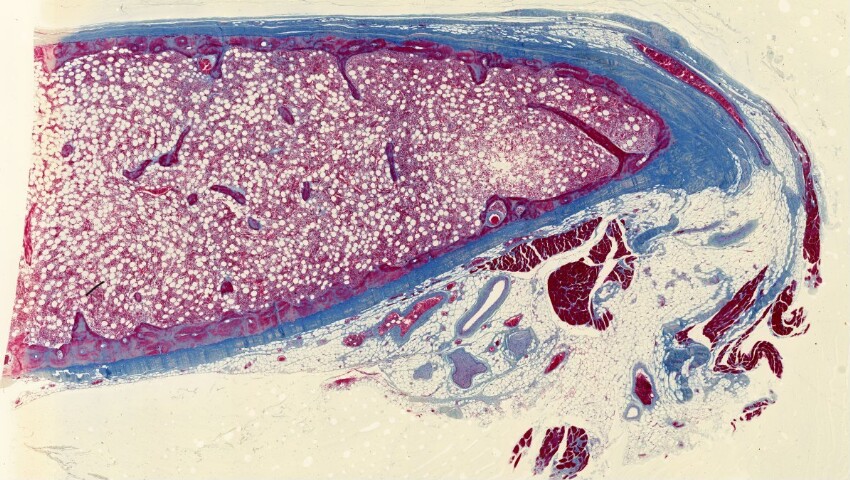

Costa di adulto. Colorazione: Azan-Mallory

Sezione trasversale di una costa di adulto.

Colorazione: Azan-Mallory.